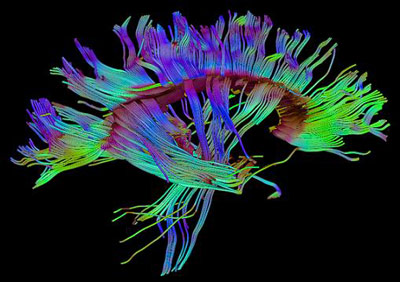

Diffusion tensor imaging (DTI) tractograpy. The color-coding of

Diffusion Tensor Imaging (DTI) - Fiber Tracking - Imagilys

Diffusion Tensor Imaging (DTI) - Fiber Tracking - Imagilys

Diffusion Tensor Imaging (DTI) revealing connectivity in the brain

Using Diffusion Tensor Imaging (DTI), axonal fiber tractography

A) Diffusion tensor imaging (DTI)-based whole-brain tractogram in